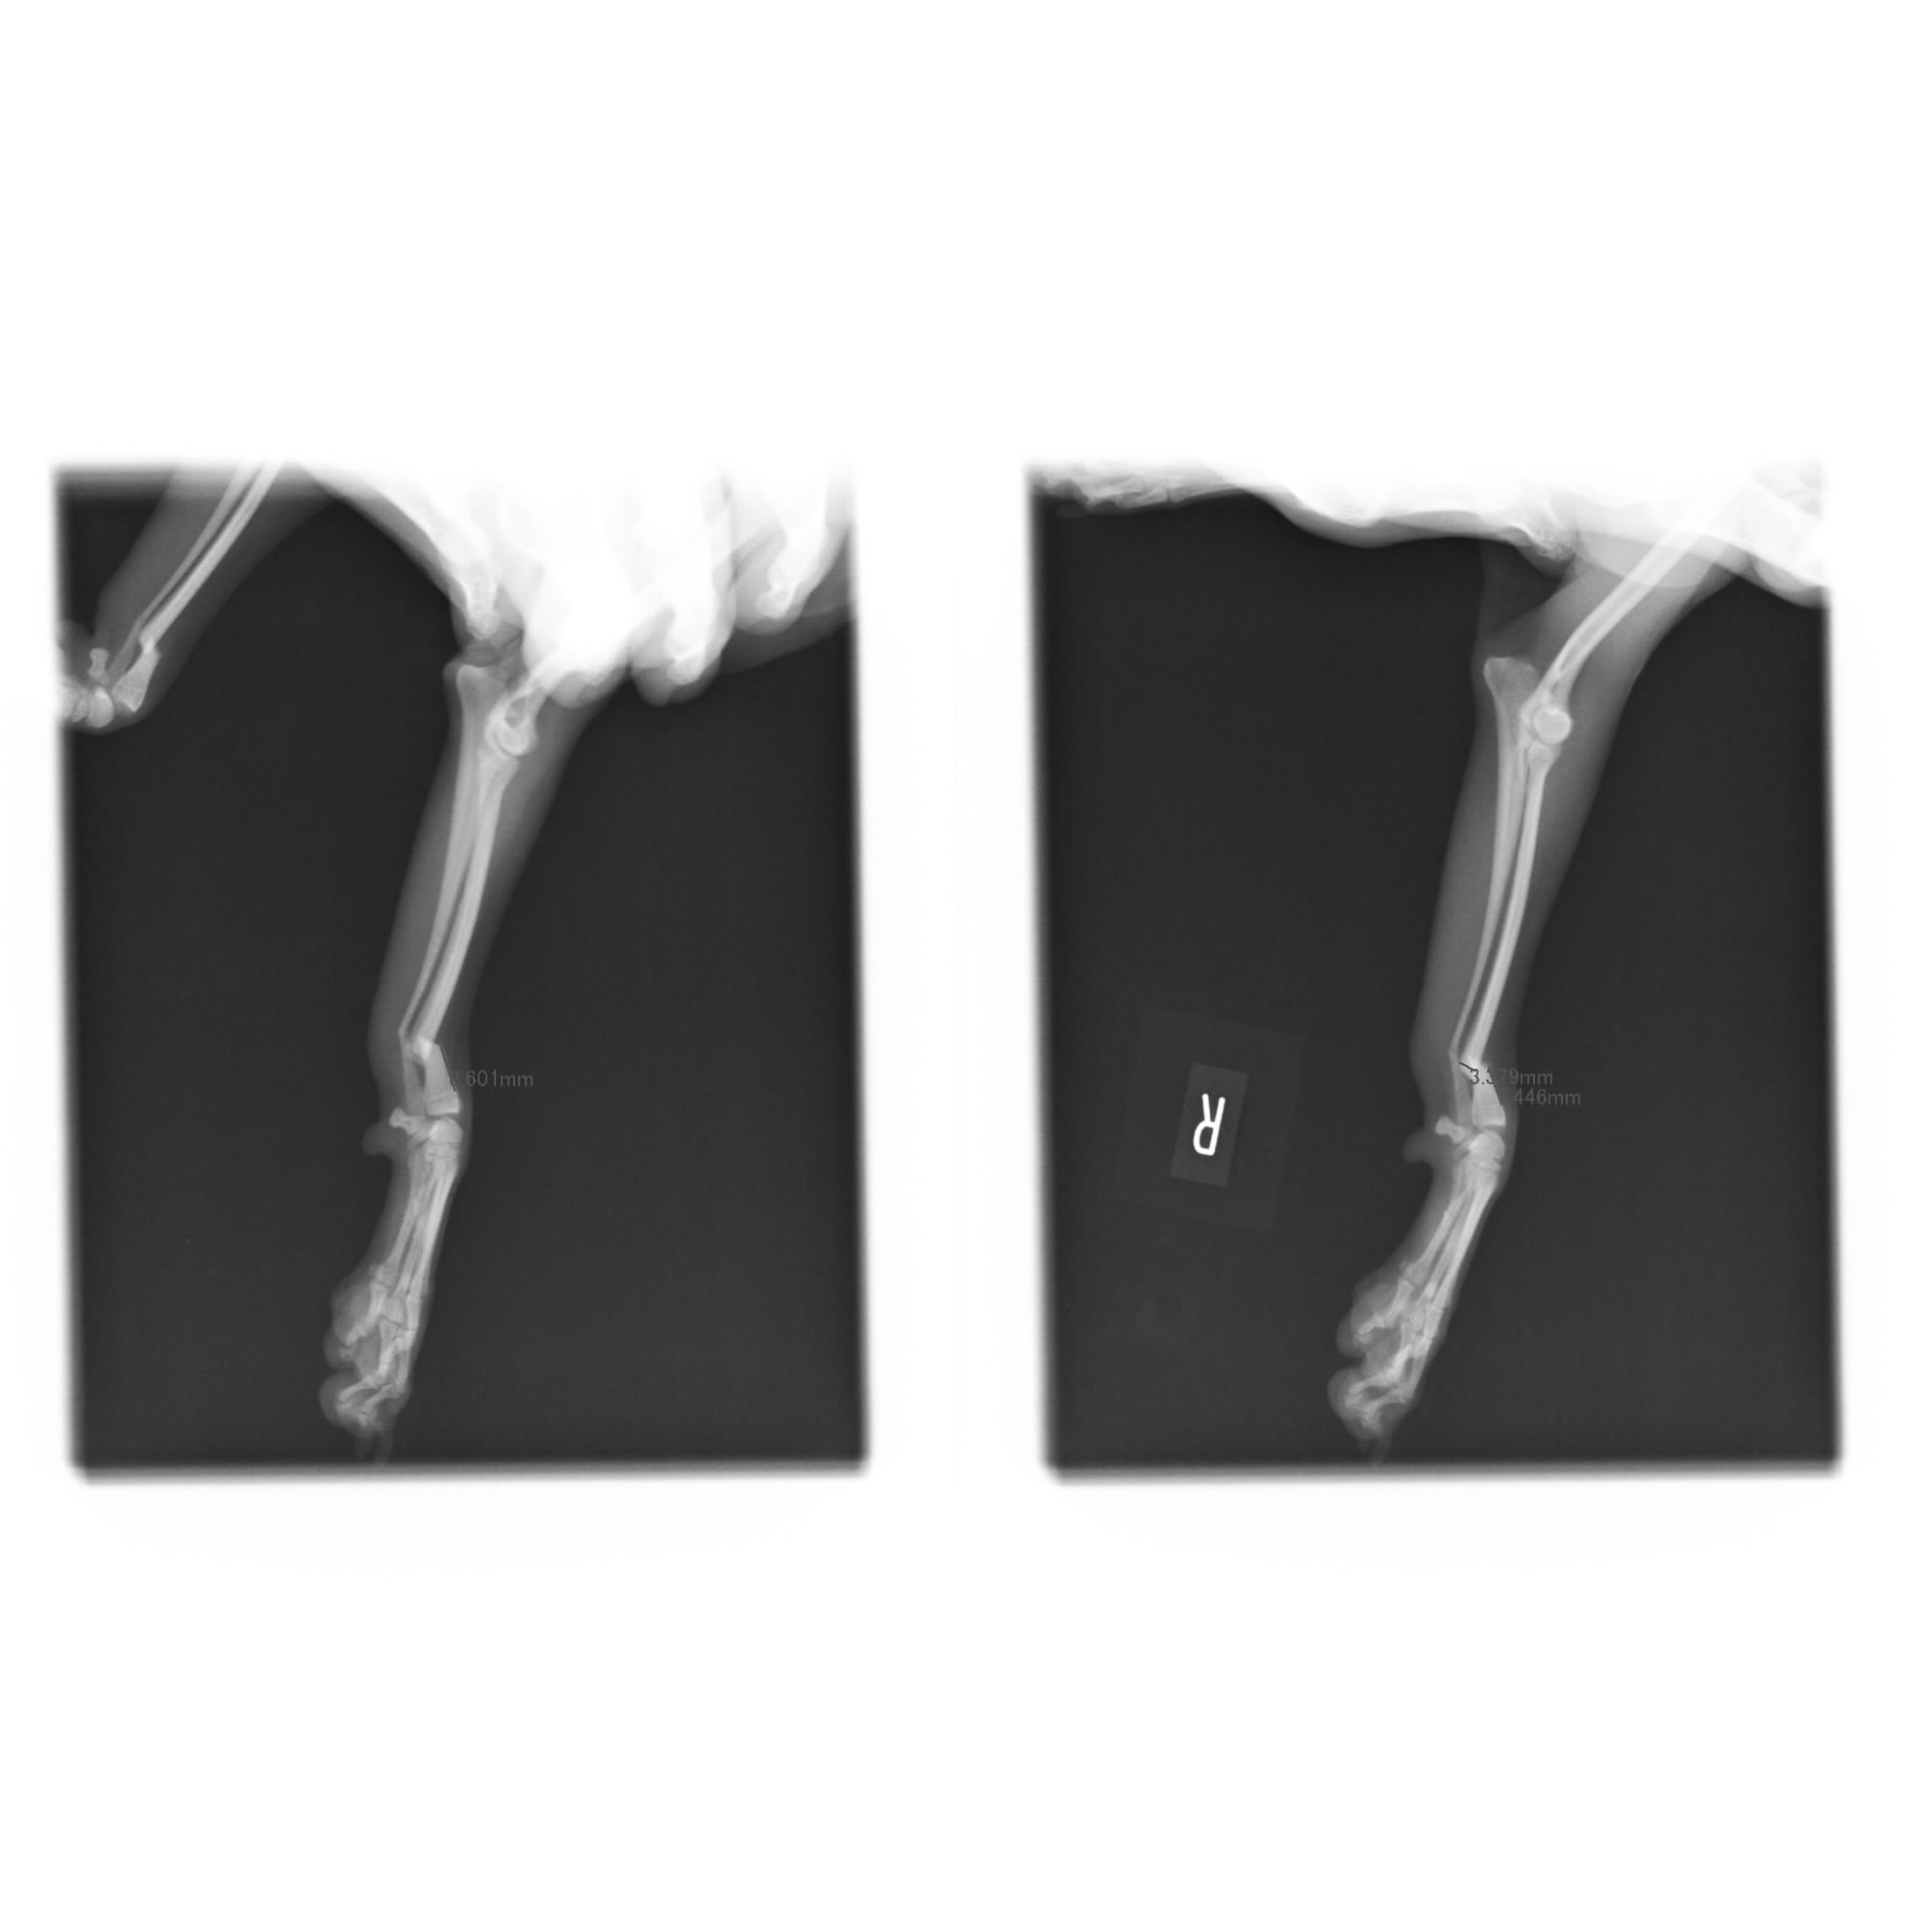

本日は両方の前足を骨折してしまった体重2kg、骨の厚み3、4mmのポメラニアンちゃんの治療をご紹介させて頂きます![]()

全く同じように見えますが、左右共に骨折してしまったレントゲン写真です![]()

骨の厚みは女性の小指よりも細いのではないでしょうか。

骨折線を慎重に合わせ、元通りの形・角度になるようにプレートをインプラントします。

非常にキレイにプレート固定出来ました![]()